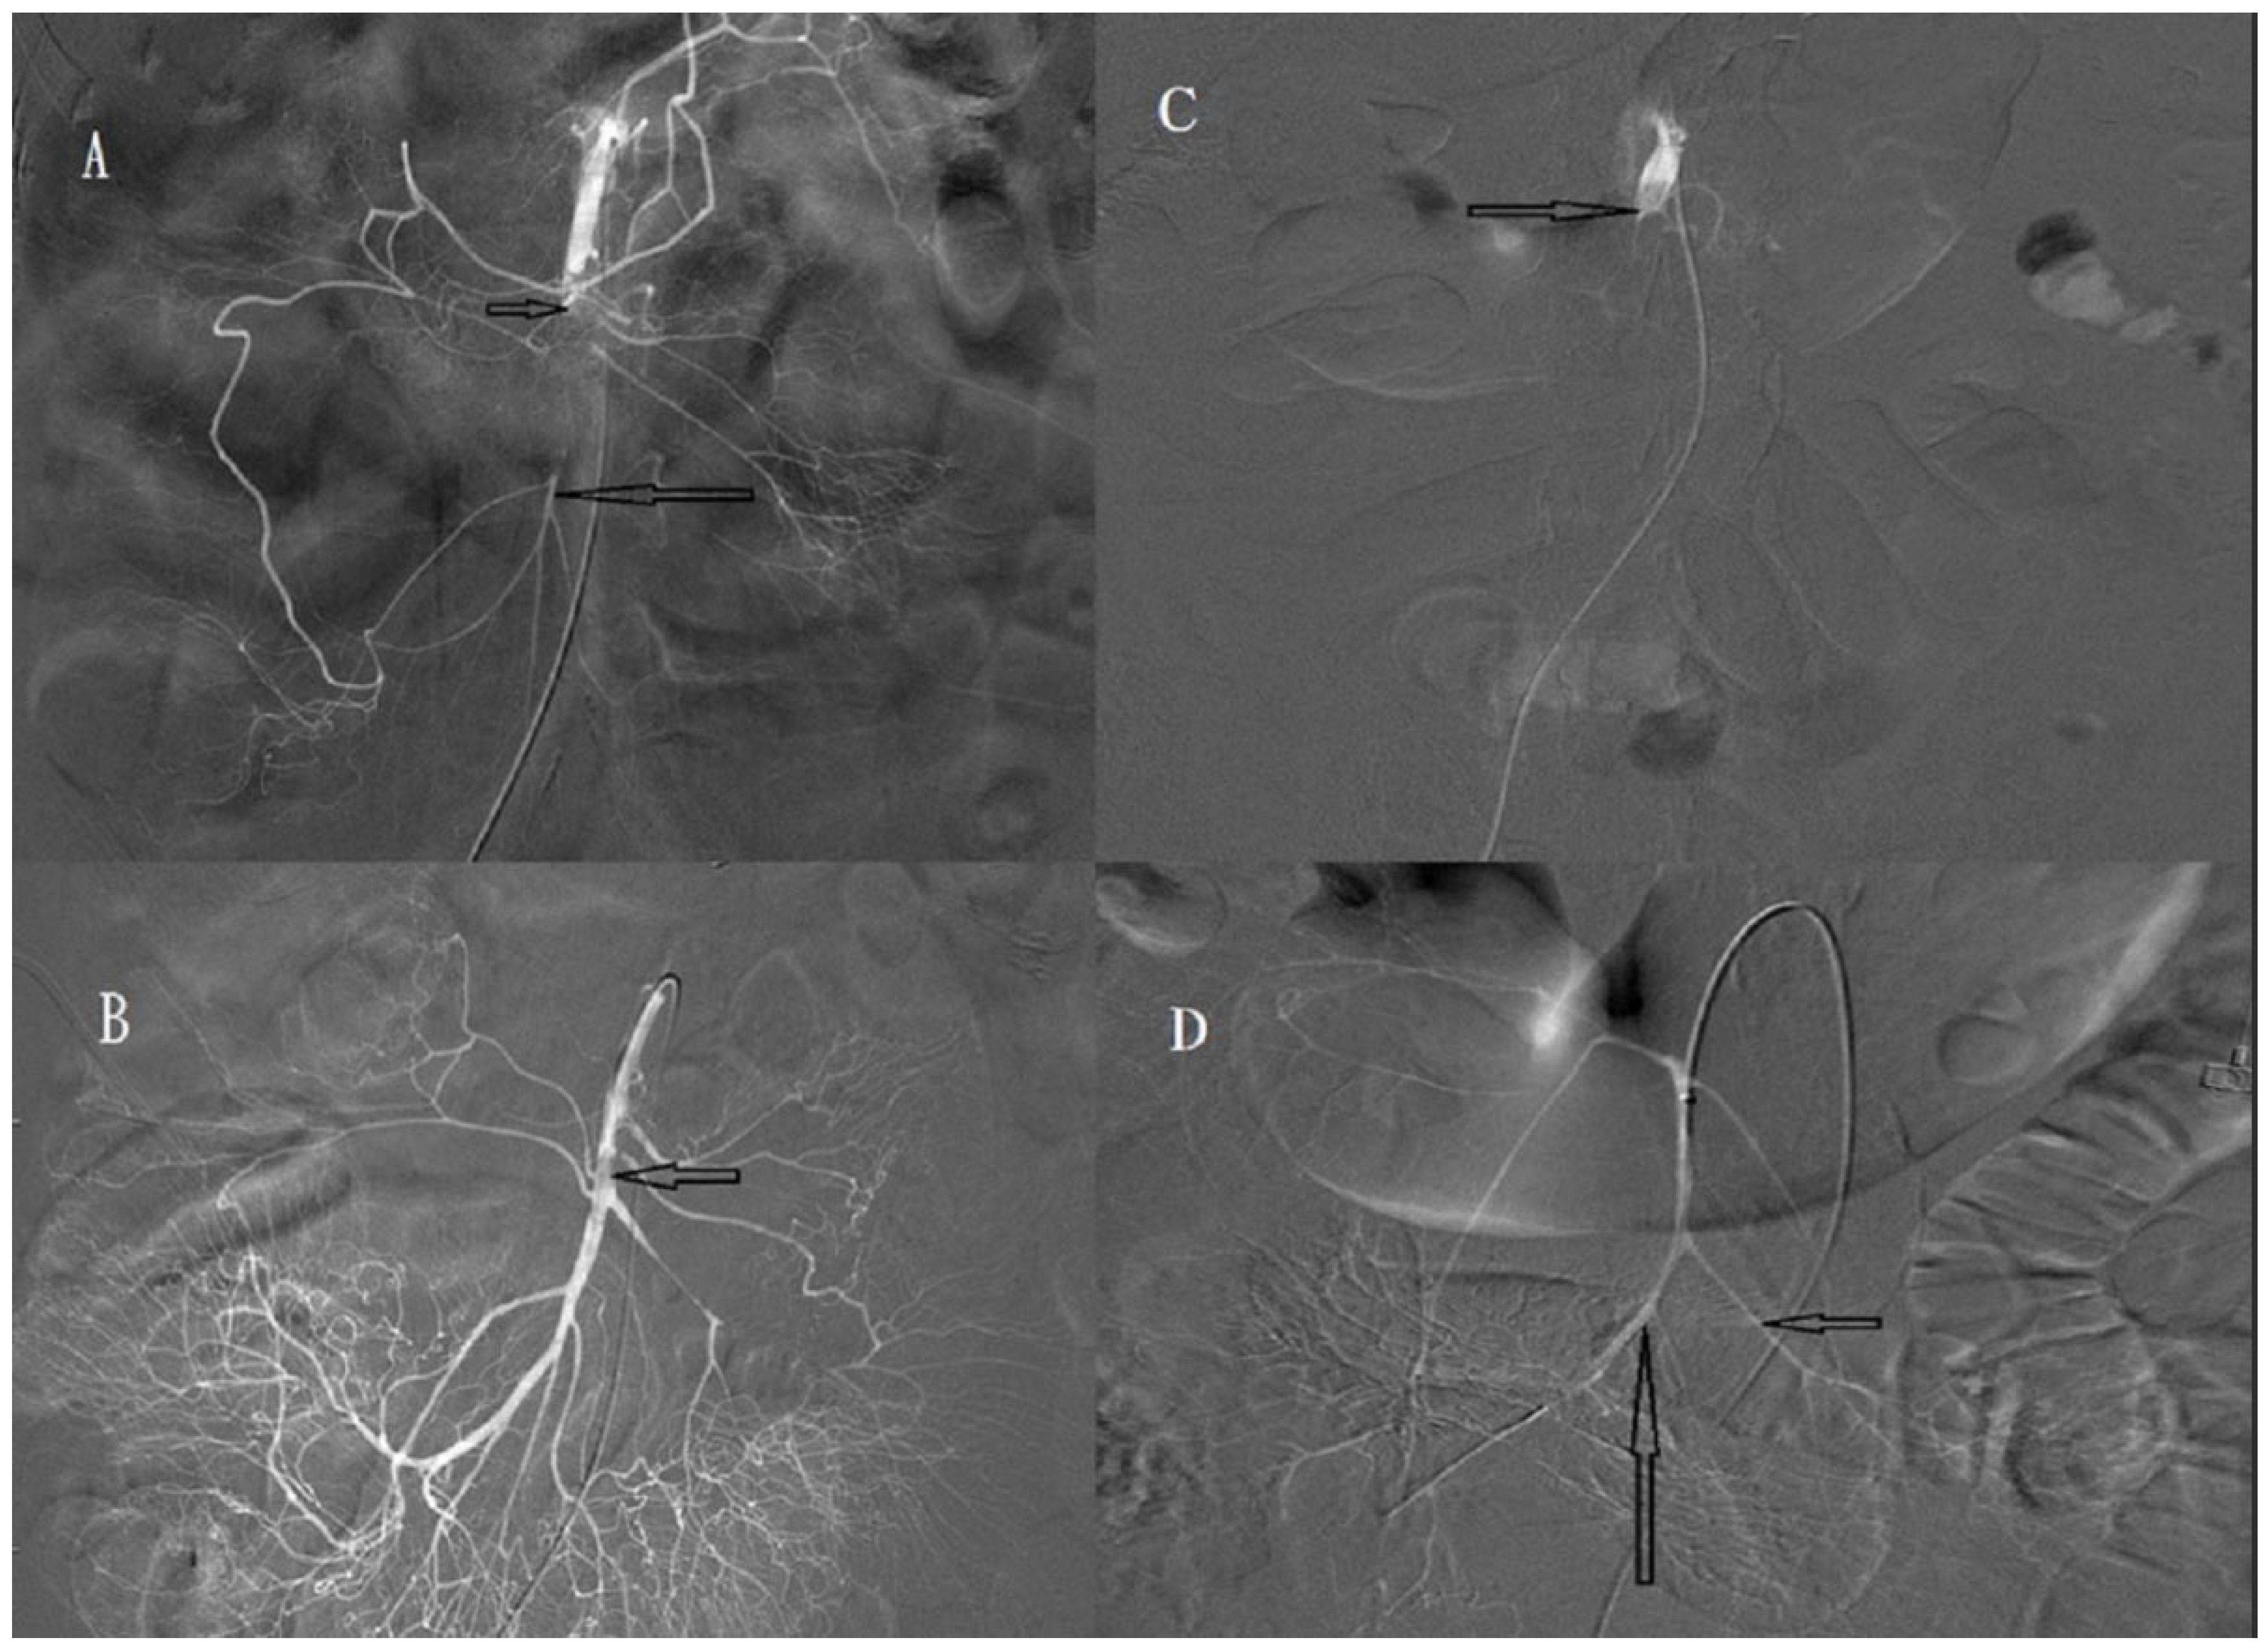

2.4. Procedure